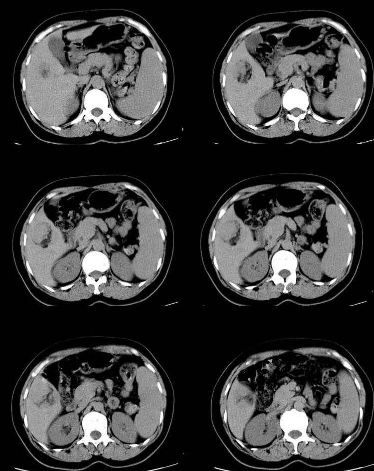

脂肪瘤圖片

脂肪瘤